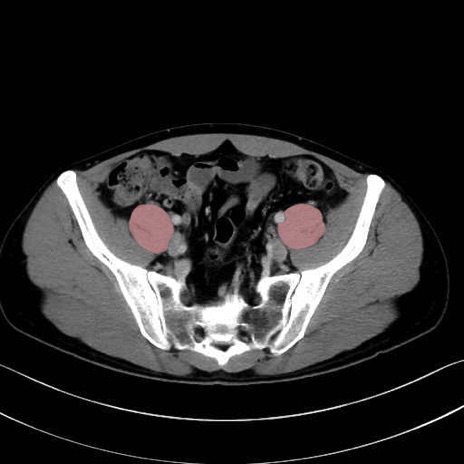

大腰筋 (Psoas major)

腸骨筋 (Iliacus)